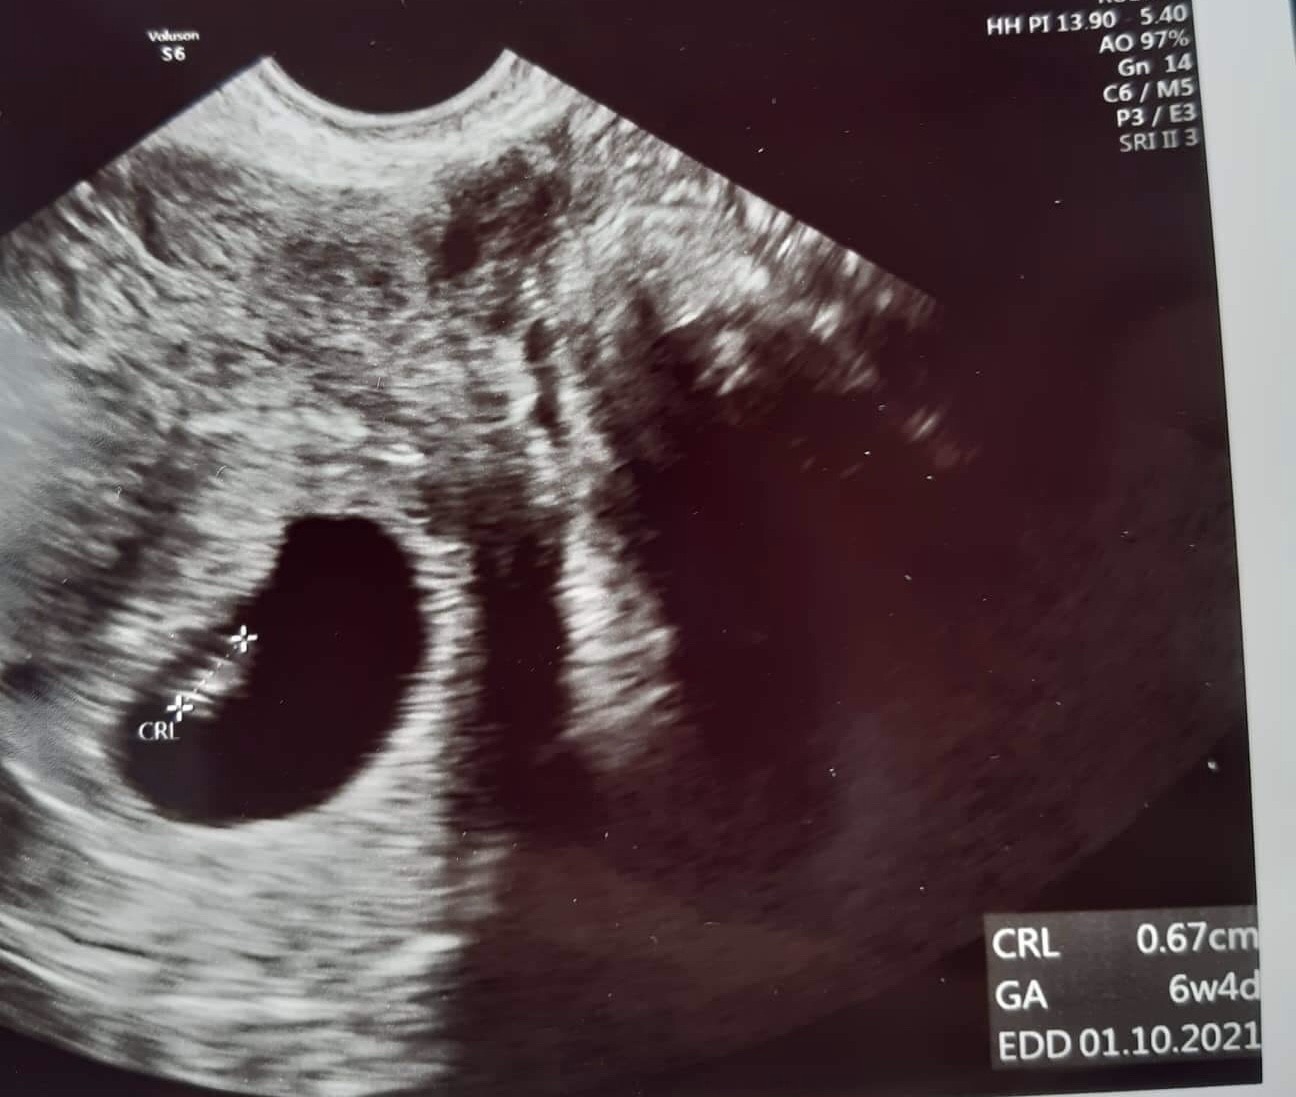

Wychodzi zatem, że jest to bardzo wczesna ciąża- 3/4t. W czwartek 04.02 umówiłam się do ginekologa prywatnie. Oczywisice wiem, że to za wcześnie na wizytę ale z uwagi na trwające u mnie leczenie kanałowe , musiałam to jak najszybciej skonsultować. Na usg nie bylo jeszcze nic widać ale doktor zauważyła,ze na lewym jajniku mam torbiel 20x23mm,a w zatoce Douglasa stosunkowo dużo płynu 27mm (płyn prawdopodobnie pojawił się po pęknięciu torbieli),endometrium niejednorodne 20mm. Pani Doktor powiedziała, że koniecznie powtórzyć usg za tydzień, żeby sprawdzić czy ilość płynu sie zmniejszyła. Powiedziała, że gdybym nagle zle sie poczuła, dostala krawienia albo ostrego bólu brzucha to mam sie nie zastawiać i jechać na sor.